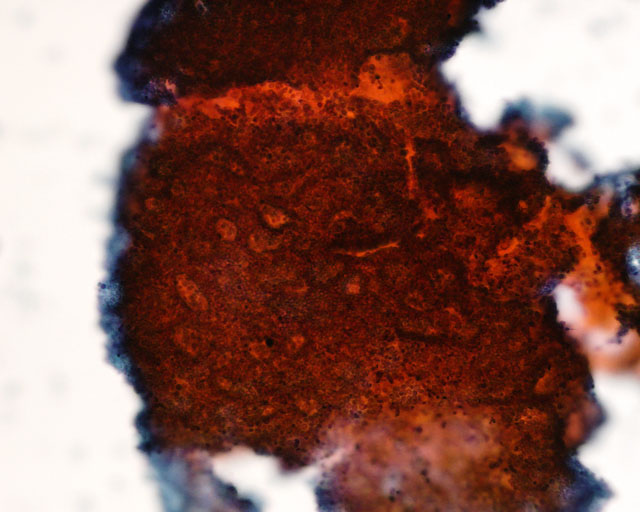

不整形や大小不同の腺腔を多く含む集塊